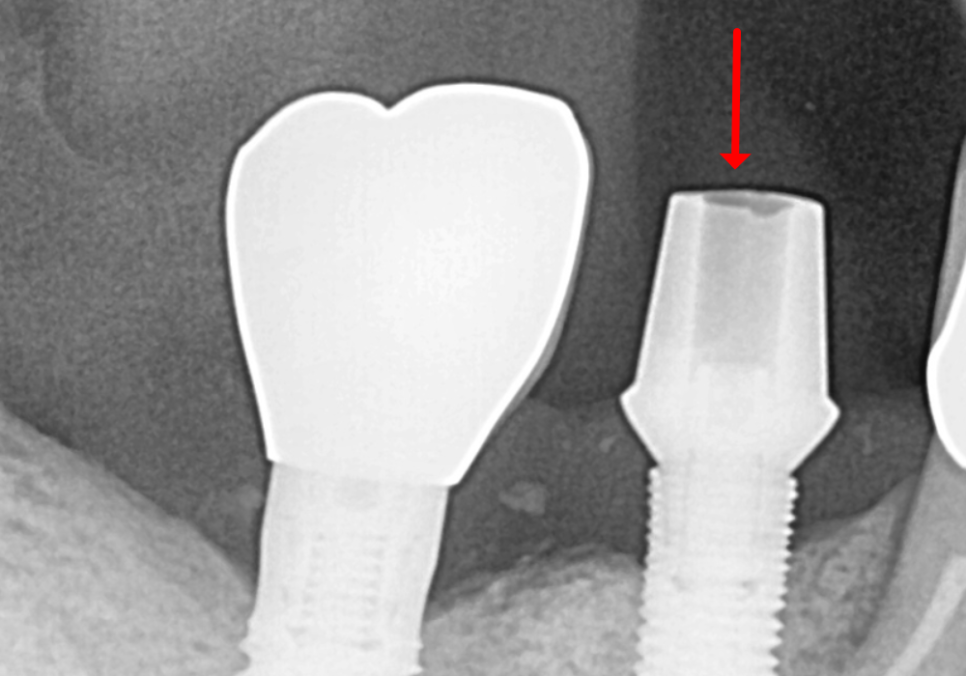

정확한 원인을 찾기 위해

엑스레이부터 찍어보았습니다.

240305

천만다행으로 임플란트의 뿌리 역할을 하는

'픽스처'와 잇몸뼈는

아주 튼튼하게 잘 붙어있었어요.

보통 임플란트가 흔들리는 이유는

크게 두 가지입니다.

고덕 치과, 임플란트가 흔들려요. 뽑아야 할까 봐 고민이라면?

염증이 생겨서 임플란트를 지탱하던

뼈가 스르르 녹아버린 경우입니다.

사실 이게 제일 골치 아픈 문제입니다.

왜냐하면 임플란트엔 신경이 없거든요.

뼈가 녹고 있어도 환자분은

아픈 줄 모르는 경우가 태반입니다.

뼈는 멀쩡한데,

머리 부분을 연결하는

나사가 풀린 경우에도

임플란트가 흔들릴 수 있습니다.

이 경우는 나사만 조이면 해결됩니다.

다행히 이 환자분은 뼈에는 문제가 없는

단순 '나사 풀림' 케이스였습니다.